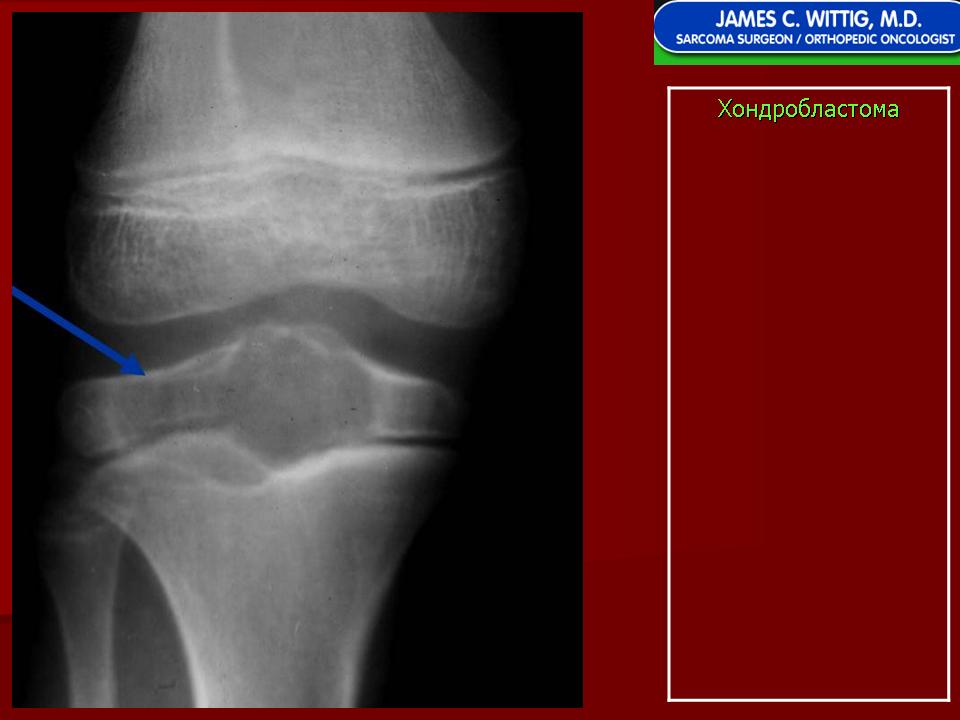

Рентгенологически хондробластома представляет собой сравнительно большой (2-4 см) очаг округлой формы, четко отграниченный от окружающей кости склеротической каймой. На фоне очага в большинстве случаев, но не обязательно определяются плотные включения, напоминающие хлопья ваты.

Рентгенологическая картина. Хондробластома выглядит как небольшой, от 3 до 6 см литический очаг, центрально или эксцентрично расположенный, с четкими контурами, занимающий около половины площади эпифизарной зоны. Хондробластома плоских костей и мелких трубчатых костей больших размеров, может сопровождаться припухлостью мягких тканей, вздутием кости и периостальной реакцией. Распространение процесса на метафизарную зону встречается часто.